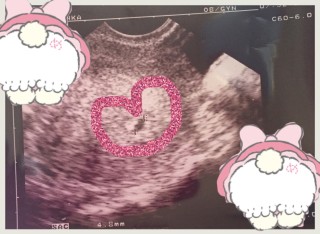

双子ちゃんです。 それぞれ7.3㎜、7.0㎜です。 しっかり元気に育ってくれることを願うばかり(^人^)